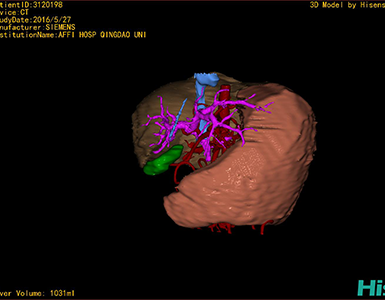

CT结果输入海信CAS系统后行3D重建及手术规划后,于2016-6-28全麻下行“劈离式肝移植(左半肝,背驮式)”手术治疗。

将0.625mm双源薄层CT资料的静脉期和动脉期Dicom格式文件导入海信CAS系统。

通过调节窗宽窗位调整CT序号,对肝实质,胆囊,下腔静脉,肝动脉、门静脉及肝静脉等进行三维重建,明确血管走行;系统自动计算肝脏体积。

模拟手术操作,肝脏体积为1052ml,通过比对11-12岁正常肝脏体积为1116.86±158.78ml,建议进行肝移植手术。

术前手术方案的规划。

术前三维重建:

重建图片